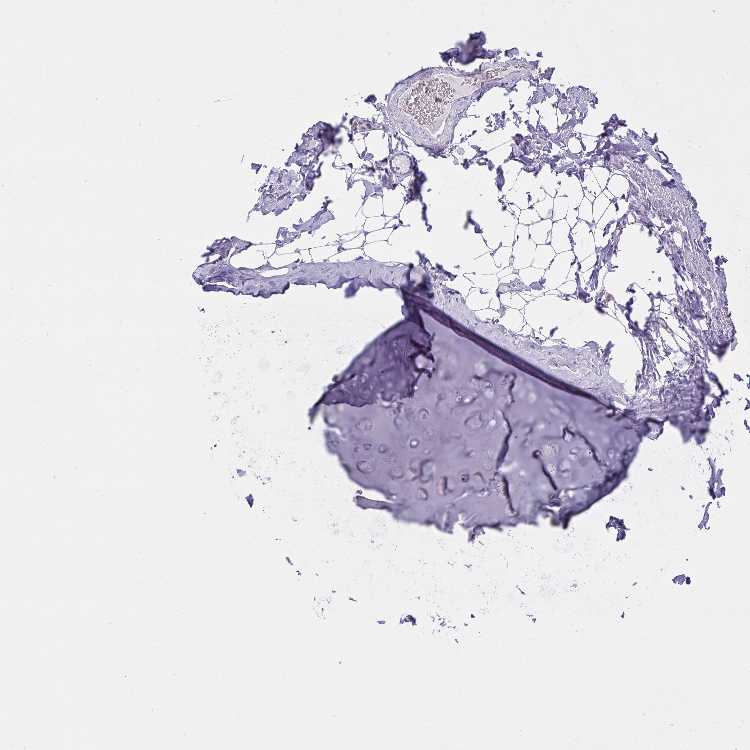

SOFT TISSUE 1 - Antibody stainingi

Antibody staining in the annotated cell types in the current human tissue is reported as not detected, low, medium, or high, based on conventional immunohistochemistry profiling in selected tissues. This score is based on the combination of the staining intensity and fraction of stained cells.

Each image is clickable and will lead to virtual microscopy that enables deeper exploration of all samples and also displays staining intensity scores, fraction scores and subcellular localization as well as patient and tissue information for each sample.

Antibody HPA056472

Chondrocytes Not detected

Fibroblasts Not detected

Peripheral nerve Not detected